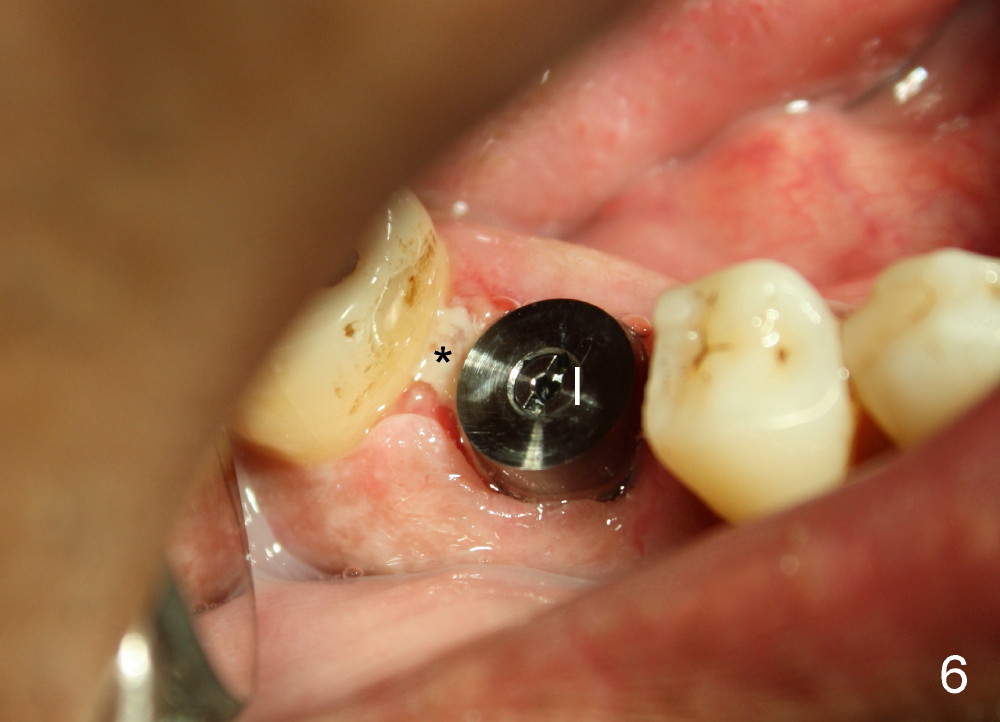

Three weeks postop, the gingiva is healthy around the implant (Fig.5 I). There is no symptom or sign of the infection (>, as compared to Fig.1). The abutment has accomplished its transient function (A, the perio dressing having dislodged) and is subsequently removed (Fig.6, to reduce micromovement of the implant and cheek and tongue bite). The 7 mm implant (I) does not look too big in its new home (alveolus). Four months postop, the mesial socket appears to have normal bony trabecular patterns (Fig.7, as compared to Fig.3).